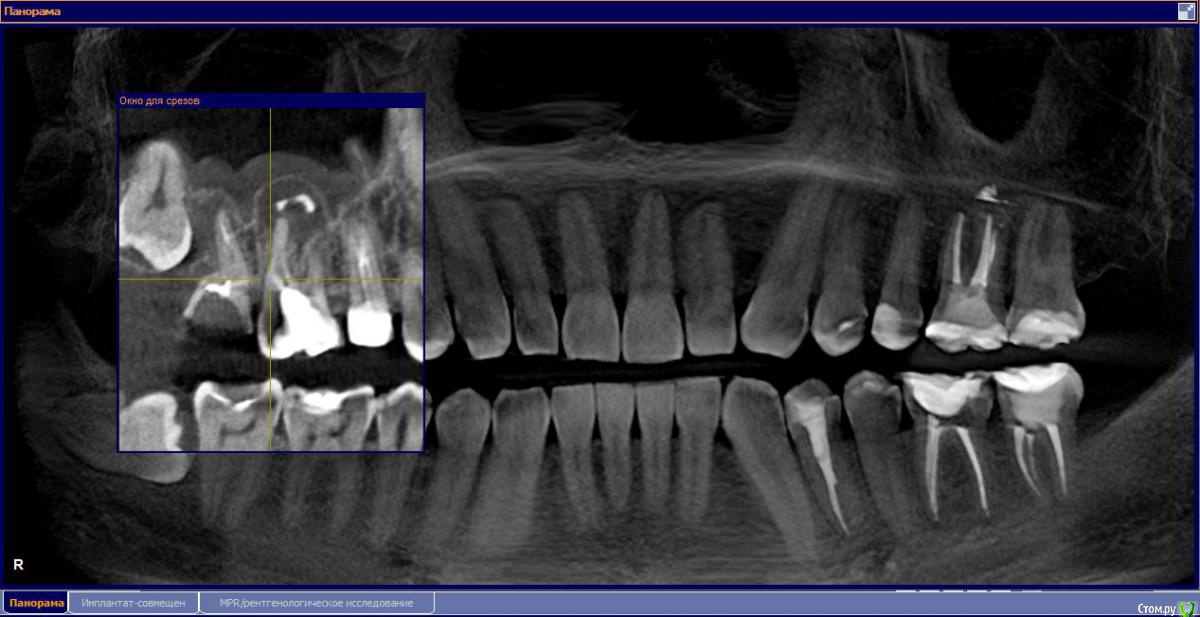

Есть ли киста? удаление 16 и 17

М, 33 года. Есть показания к одновременному удалению 16-го зуба - киста, и 17-го - разрушена верхушка. 8-й предлагают оставить, чтобы "держал кость" (как то так мне озвучили).

Через 3-4 месяца рекомендуют синус-лифтинг и установку двух имплантатов.

Сейчас десна вокруг 18 и 17 зубов воспалена. На операцию через пару дней..

- Возможно ли консервативное перелечивание 16 зуба и есть ли смысл?

- Насколько опасная имеется киста?

и 6 и 7й зубы не выглядят 100% кандидатами на удаление.

1.6 большая вероятность сохранить,но понятнее при очном осмотре и диагностическом вскрытии. 1.7,скорее всего,не жилец,но тоже очно взглянуть на него стОит